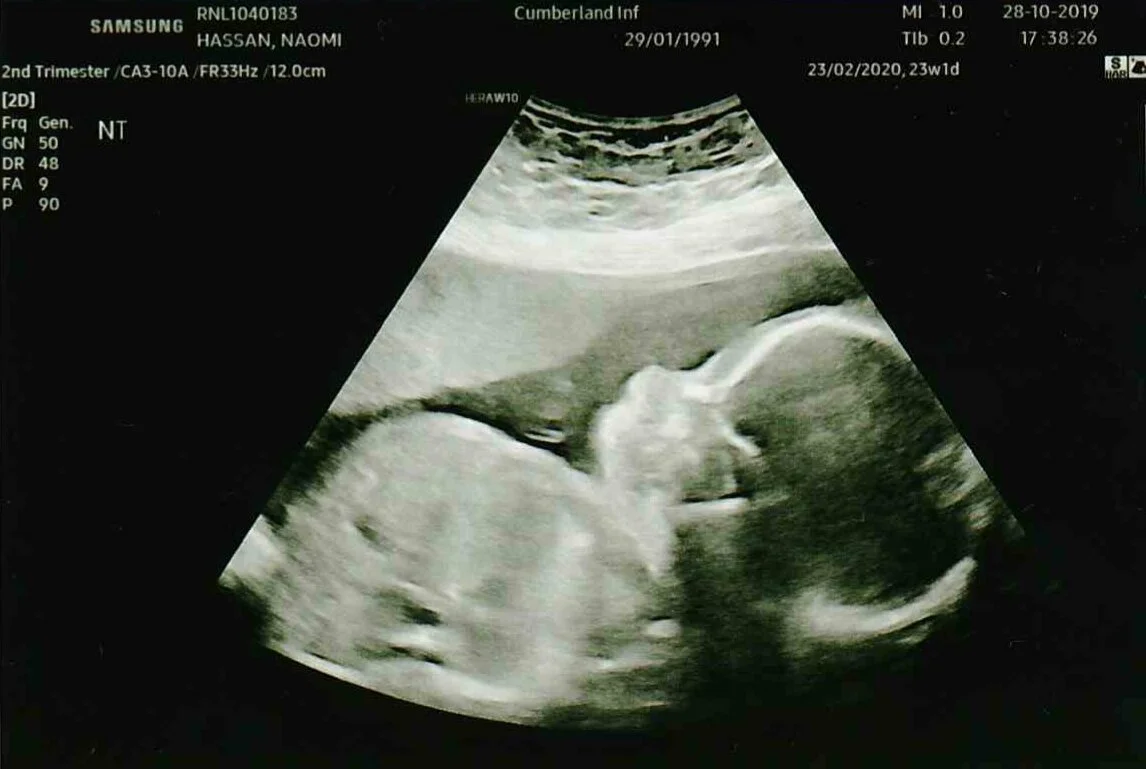

Pin On Diy Crafts from i.pinimg.com See more of ultrasound dimensions: As well as feeling and looking more pregnant you'll be offered blood tests and your second ultrasound scan at around 20 weeks. Your seventh week of pregnancy. This is called the dating you may need to have a full bladder for this scan, as this makes the ultrasound image clearer. At 23 weeks pregnant, your baby is 8 inches (crl), over 11 inches in height, and weighs 20 ounces. You can hear baby's heartbeat through a stethoscope and you may start having pregnancy if you're 23 weeks pregnant, you're in month 6 of your pregnancy. A guide on pregnancy at 23 weeks with information on what to expect, baby development, and symptoms. We offer 3d/4d scan online booking option for you.

This scan just showed that the babies still looked normal and when i was 23 weeks along, i had a fetal wellbeing scan.

As your baby becomes more active, you'll notice him or her kicking, hitting, or punching you more often. Most of her snooze time — about 80 percent of it, actually — will. Use the first day of your last menstrual cycle (lmp) to work out when you most likely conceived, how many weeks pregnant you are, and when your baby's birth is expected. It's week 23, just a little past the halfway point of your pregnancy. That's why doctors refer to your stage in pregnancy by week, not month. This is called the dating you may need to have a full bladder for this scan, as this makes the ultrasound image clearer. Listen to your doctor's advice, follow his recommendations for a. At 23 weeks pregnant, your baby is the size of a grapefruit. Follow my journey from bump to bubba number two! See more of ultrasound dimensions: This scan looks at how the baby is growing and whether there. A guide on pregnancy at 23 weeks with information on what to expect, baby development, and symptoms. We offer 3d/4d scan online booking option for you.

A guide on pregnancy at 23 weeks with information on what to expect, baby development, and symptoms. Your baby weighs just over a pound this week! How big is my baby at 17 weeks pregnant? You're probably looking pregnant, so be prepared for comments about looking too big or too thin, or hopefully just. It can get confusing, we know—those 40 weeks of pregnancy don't break out cleanly into nine months. At 23 weeks pregnant, your baby weighs around a pound, though you have probably gained around 12 to 15 pounds. Sexing scans are highly reliable but can be. You can ask your midwife or doctor before the scan if this is. Ultrasound at 23 weeks pregnancy. Follow my journey from bump to bubba number two! Your first scan is more likely to be a dating scan when you're between about 10 weeks and 14 weeks pregnant. A ct scan during pregnancy may be necessary and doctor recommended. As well as feeling and looking more pregnant you'll be offered blood tests and your second ultrasound scan at around 20 weeks.